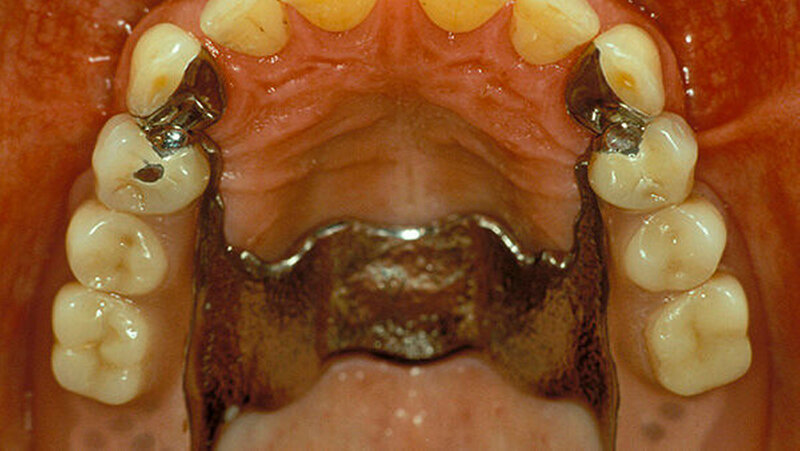

Beispiele für individuellen ZE

Die Jahrestagung der Deutschen Gesellschaft für Prothetische Zahnmedizin und Biomaterialien (PGPro) in Ulm geht der Frage nach, welche Versorgungskonzepte - mit guten Langzeitergebnissen - individuell und preiswert machbar sind. Gute Beispiele finden Sie in unserer Bilderstrecke!